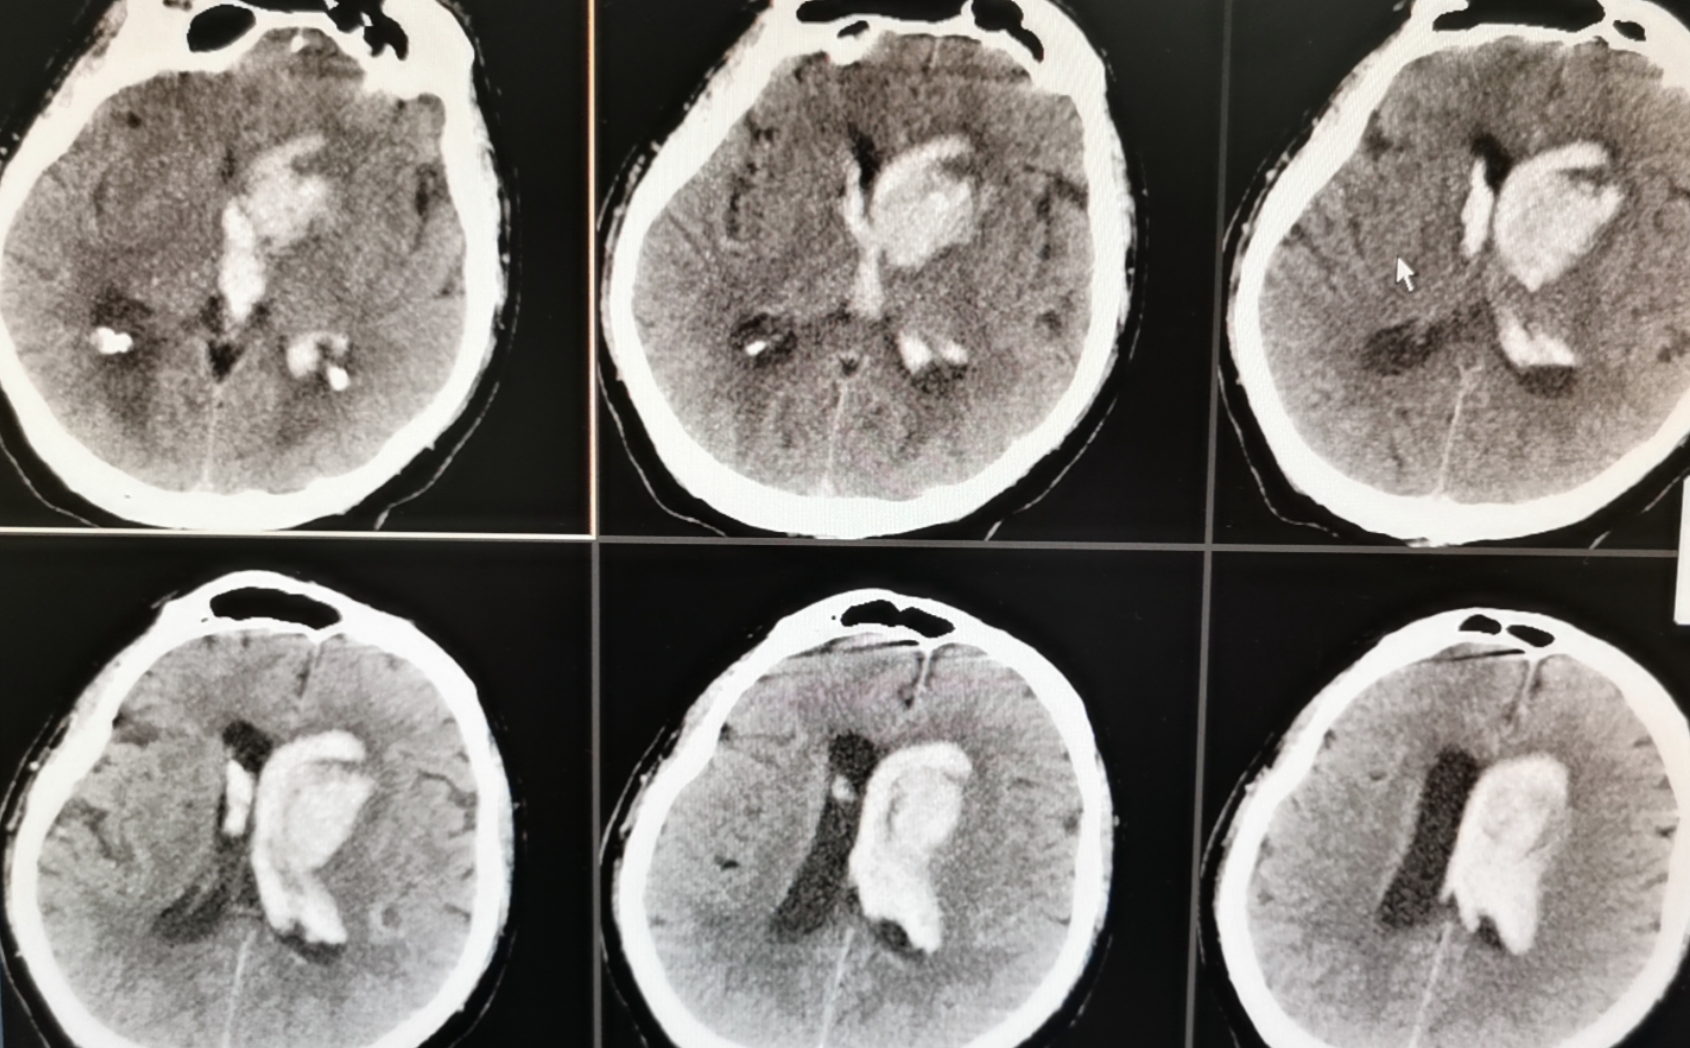

术后显示血肿清除满意

神经内镜微创治疗高血压脑出血